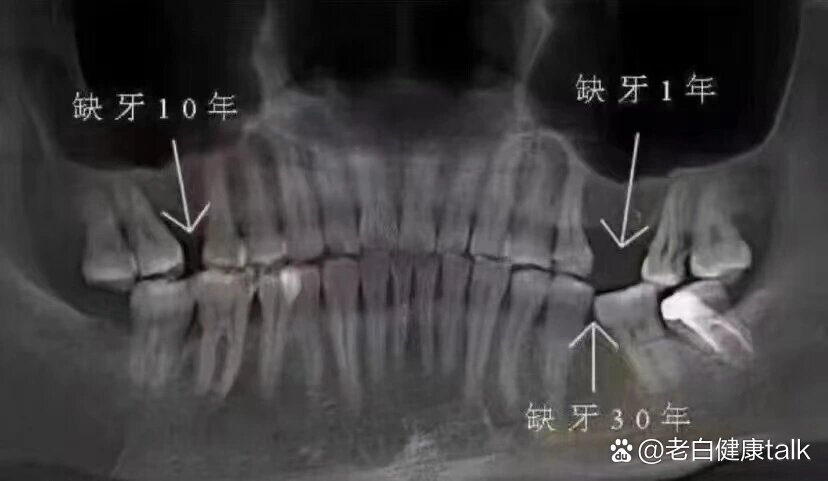

牙齿长期缺失不补,对颌牙伸长至脱落真不是危言耸听!

缺牙不及时去种牙就会导致对颌牙伸长,垂直间隙过小,给种牙带来难度